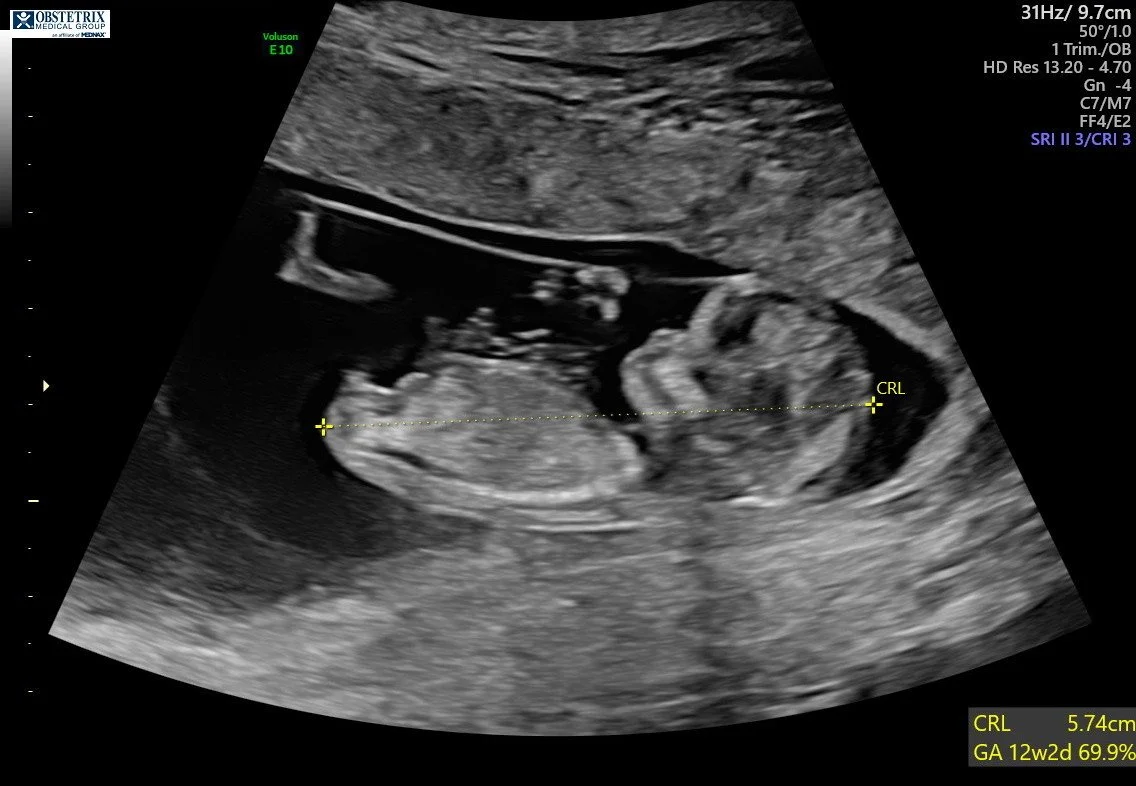

I am currently 14 weeks pregnant as I write this blog post. Once again, I truly appreciate all of you for being so supportive of me during this journey. Throughout this process, I will do my best to keep you all updated on my pregnancy.